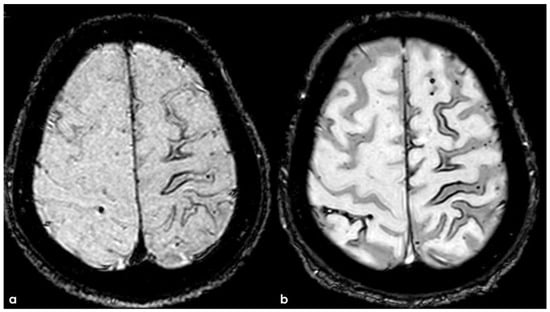

6. December 2017: Recurrent SAH